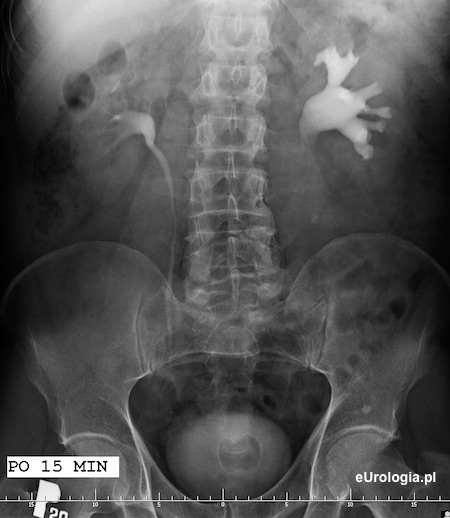

15 minuta po podaniu kontrastu - zakontrastowany UKm nerki prawej i górny odcinek prawego moczowodu. wodonerczowo poszerzony UKM lewej nerki